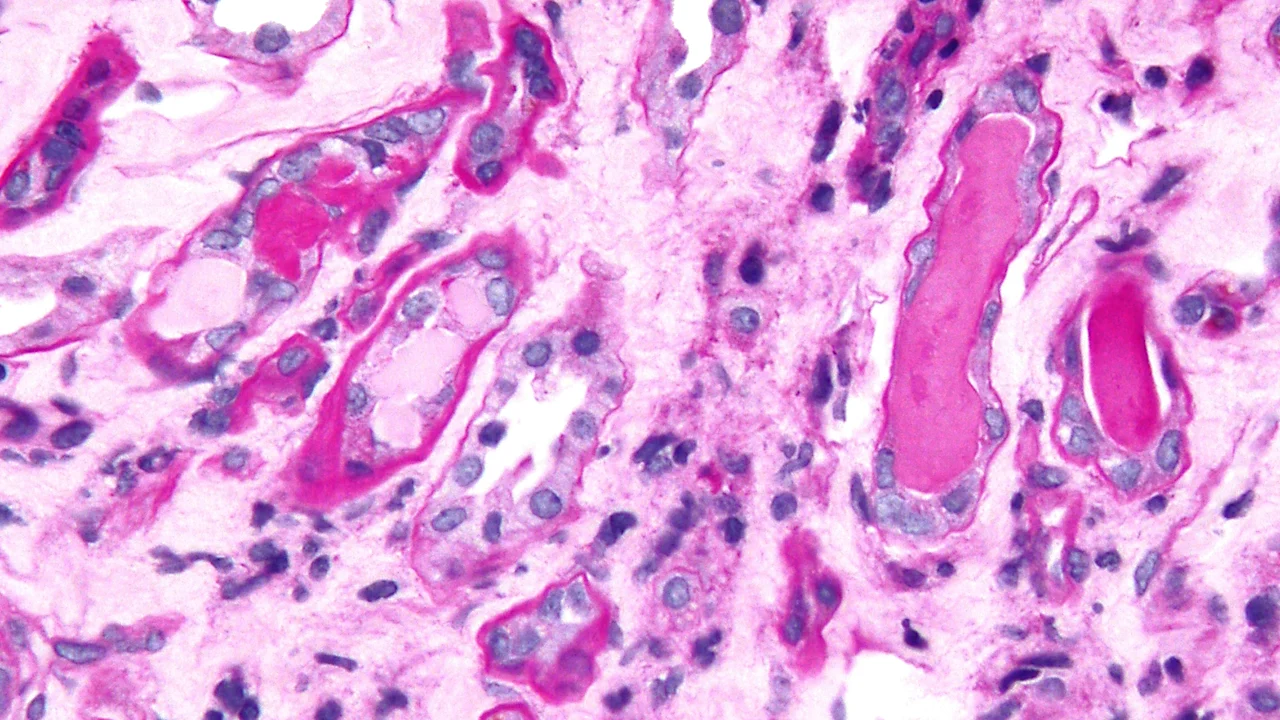

المايلوما المتعددة (مم) هي سرطان الدم الذي يؤثر على خلايا البلازما في الجسم ، مما يؤدي إلى تحويرها وتنمو بشكل لا يمكن السيطرة عليها في نخاع العظام. تنتج خلايا البلازما هذه الأجسام المضادة غير الطبيعية التي تسمى “بروتينات M” التي تسبب الفوضى على الجهاز المناعي والكلى والعظام.